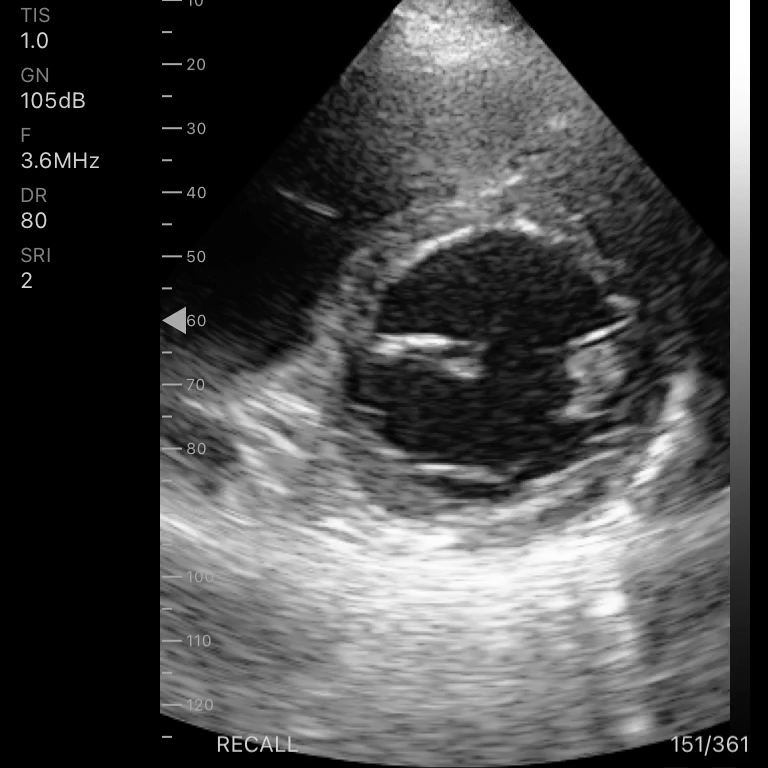

Tipo de sonda: Arreglo en fase

Frecuencia: 1 – 4 MHz

Modos de escaneo: B, B/M, Color, PW

Profundidad de pantalla: 90 – 190 mm

Mediciones: Longitud, área, velocidad, FC, S/D, LVIDd, LVIDs, SV, EF